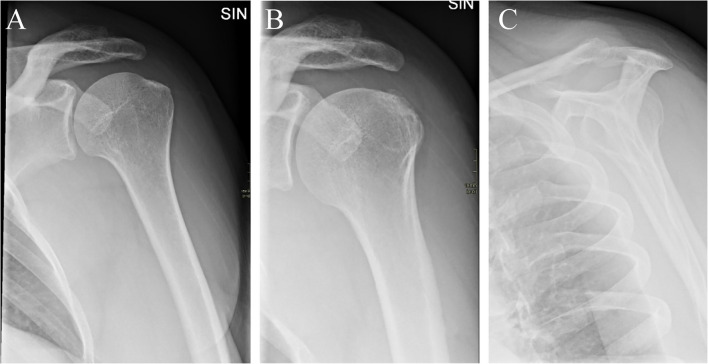

目的:研究疑似肩峰下撞击综合征(SIS)患者的特定x线表现与患者报告的肩部疼痛和残疾之间的关系。材料和方法:本横断面研究采用前瞻性研究的基线数据。研究人群包括年龄在18至63岁之间,因怀疑SIS而转诊到骨科诊所的患者。首次到骨科就诊前的影像学检查包括肩峰下钙化、肩峰形态特征(即肩峰类型和骨刺)、肩锁骨关节炎、既往肩关节脱位的迹象(Bankart/Hill-Sachs病变)和建筑测量(即肩峰倾斜、肩峰指数和肩峰外侧角)。采用牛津肩关节评分(OSS)对患者首次到公立骨科就诊时或SIS手术前的问卷回答进行肩部疼痛和残疾评估。低OSS被定义为具有评分结果:人群包括825例患者。从x线检查到完成问卷的中位时间为9天(SD = 27.1)。在校正分析中,我们发现侧骨刺,特别是鸟喙型(OR = 2.24 (95% CI 1.36-3.71)), Bankart/Hill-Sachs病变(OR = 2.49 (95% CI 1.38-4.48))和肩峰倾斜bbb35°(OR = 0.62 (95% CI 0.41-0.94))具有统计学意义。女性(OR = 2.25 (95% CI 1.59-3.18))也与低OSS相关。结论:就患者报告的肩部疼痛和残疾的相关性而言,侧刺,重点是鸟喙型,Bankart/Hill-Sachs病变和肩峰倾斜bbb35°,在临床上似乎很重要。

Materials and methods: This cross-sectional study used baseline data from a prospective study. Study population included patients age 18 to 63 years, referred to orthopaedic clinic on suspicion of SIS. Radiographic findings before first visit to a department of orthopaedic surgery comprised subacromial calcifications, acromial morphological characteristics (i.e. acromial type and spur), acromioclavicular osteoarthritis, signs of previous glenohumeral dislocation (Bankart/Hill-Sachs lesions), and architectural measures (i.e. acromial tilt, acromion index, and lateral acromial angle). Shoulder pain and disability were evaluated using the Oxford Shoulder Score (OSS) from patient's response to a questionnaire at first visit to the public department of orthopaedic surgery or before surgery for SIS. A low OSS was defined as having a score < 25. Associations between the radiographic findings and low OSS were analysed using logistic regression.

Results: The population comprised 825 patients. Median time between radiographic examination and completion of the questionnaire was 9 days (SD = 27.1). In adjusted analysis, we found a statistically significant association for lateral spur especially birdbeak type (OR = 2.24 (95% CI 1.36-3.71)), Bankart/Hill-Sachs lesion (OR = 2.49 (95% CI 1.38-4.48)), and acromial tilt > 35° (OR = 0.62 (95% CI 0.41-0.94)). Female sex (OR = 2.25 (95% CI 1.59-3.18)) was also associated with low OSS.

Conclusion: In terms of associations with patient-reported shoulder pain and disability, lateral spurs, with emphasis on birdbeak type, Bankart/Hill-Sachs lesions, and acromial tilt > 35°, seemed clinically important.